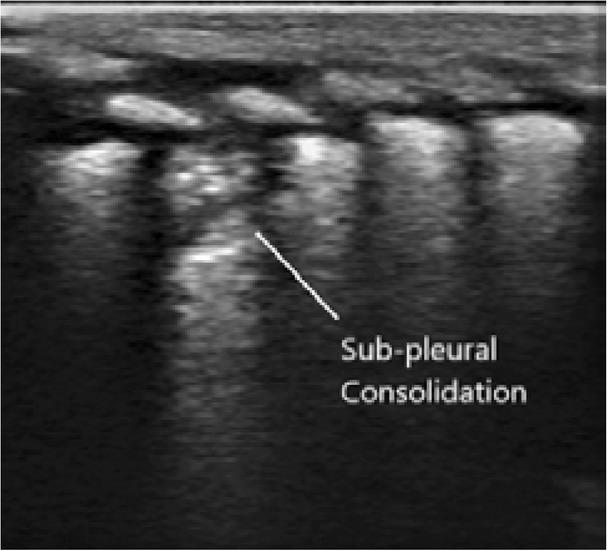

Fig. 1